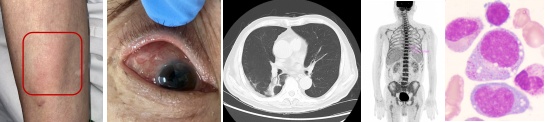

在2020年12月,Beck[1]等人发现了一种与UBA1基因突变相关的自身炎症性疾病,被命名为VEXAS(空泡、E1酶、X-连锁、自身炎症、体细胞)综合征。这是一种严重的进行性疾病,通常在中老年期发病,常伴有发热,并可能累及皮肤、软骨、肺、血管等多个器官,合并血液系统疾病如巨幼细胞贫血、血小板减少症、静脉血栓、血液系统恶性肿瘤等(见下图)。临床上,VEXAS 综合征表现复杂,容易被误诊或误治。

VEXAS 综合征的临床表现(图源:如图示)